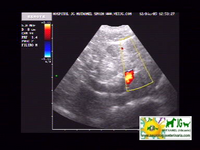

ecografía donde se aprecian las neoplasias hepáticas |

intentamos buscar el shunt portosistémico, pero no es visible ni con el doppler |

Se aprecia la vena porta muy aumentada de tamaño y sinuosa, por lo que es previsible que haya shunts, aunque no los distingamos |